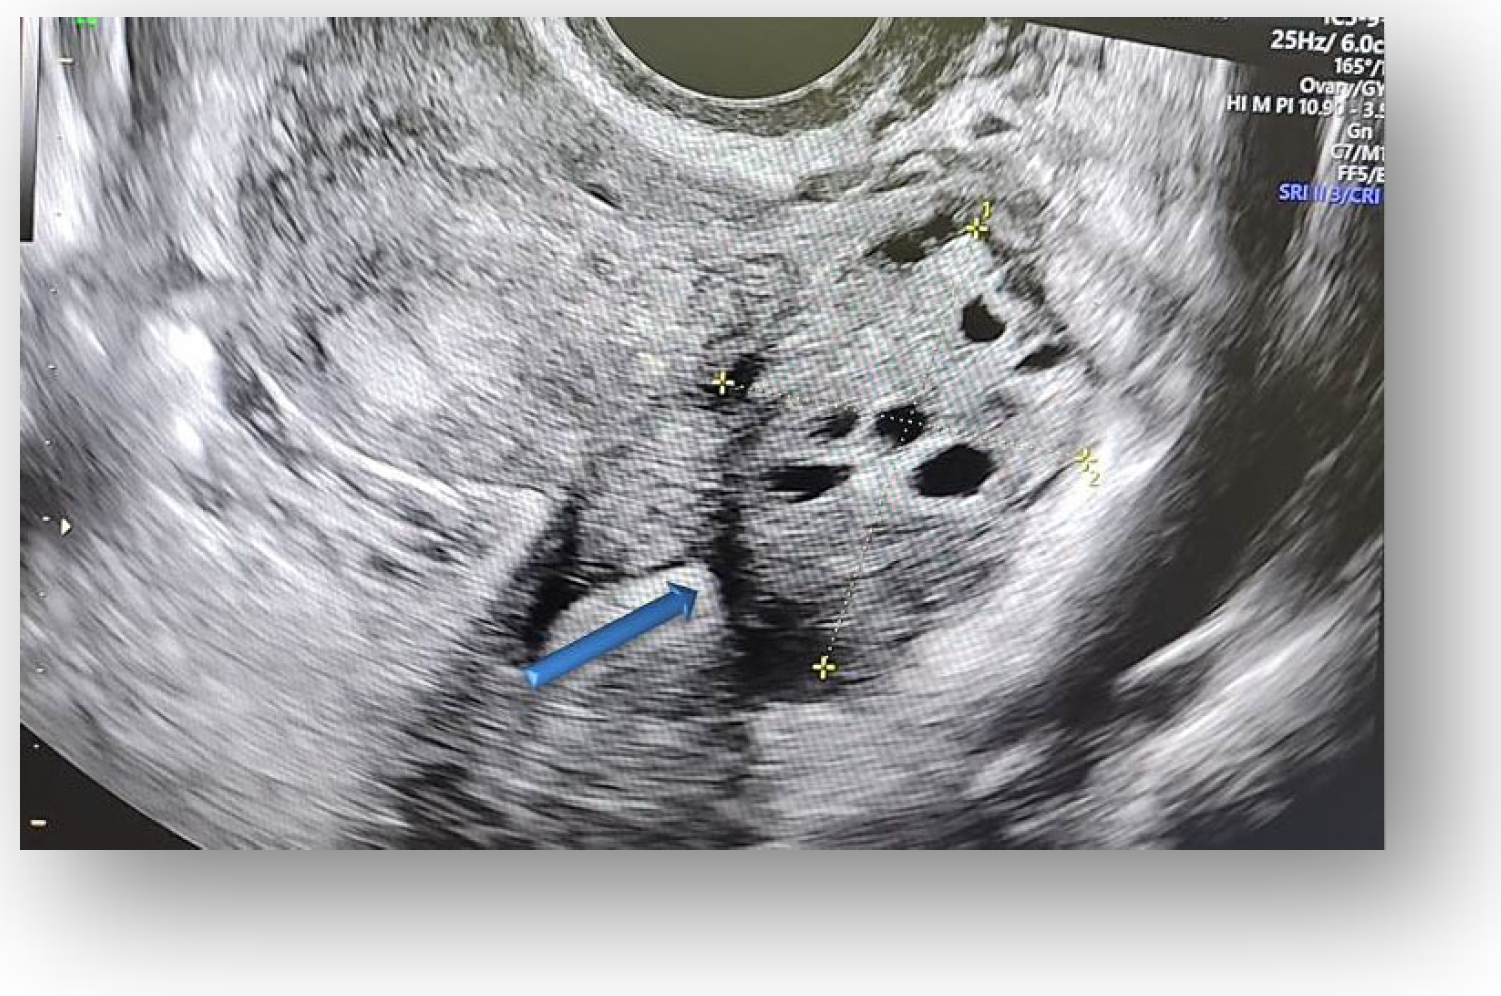

Considering all the information gathered, we first decided to perform an ultrasound (US) which revealed a large hypoechoic cystic formation on the left of the uterus, misdiagnosed as a paraovarian cyst measuring 80 mm (Figure 1, Figure 2, Figure 3 and Figure 4).

Figure 2.

Hypoechoic cystic formation with peripheral doppler flow, without intracystic vegetations.